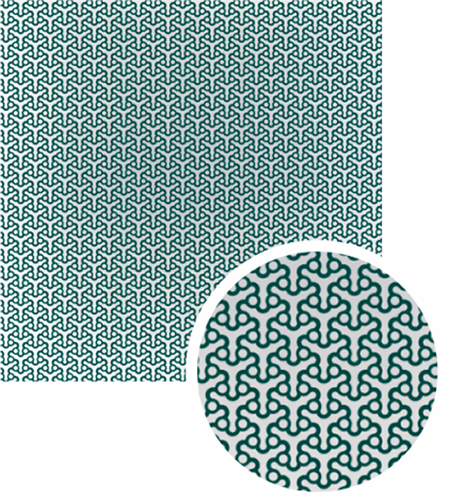

Implant material

- Commercially pure titanium

- Ultra-high strength

- Excellent biocompatibility

- Radiopaque

- Autoclavable – withstands repeated sterilization

- Requires the use plates and screws are used to attach the patient specific implant to native bone.